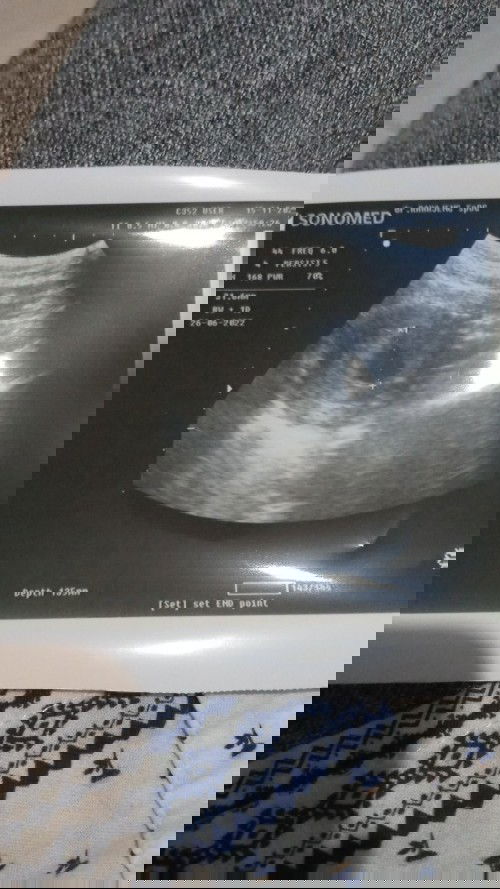

#firstbaby #pleasehelp halo bun mau tanya... aku hamil udah masuk w10, tp usg sama dokter bilang size nya kyk umur 8w, nah sejak 3-4 hari lalu pendarahan dikit sama kluar jaringan gitu, kadang nyeri ringan kadang gak, udah d kasik obat penguat rahim tp efek nya aku jd sakit gigi, pdhal seumur2 belum pernah sakit gigi dokter bilang 2 minggu lg suruh cek kontrol, tp kalo keadaan gini sebelum 2 minggu apa gpp periksa lg bun? jujur aku takut sama kepikiran :( takut adek kenapa2